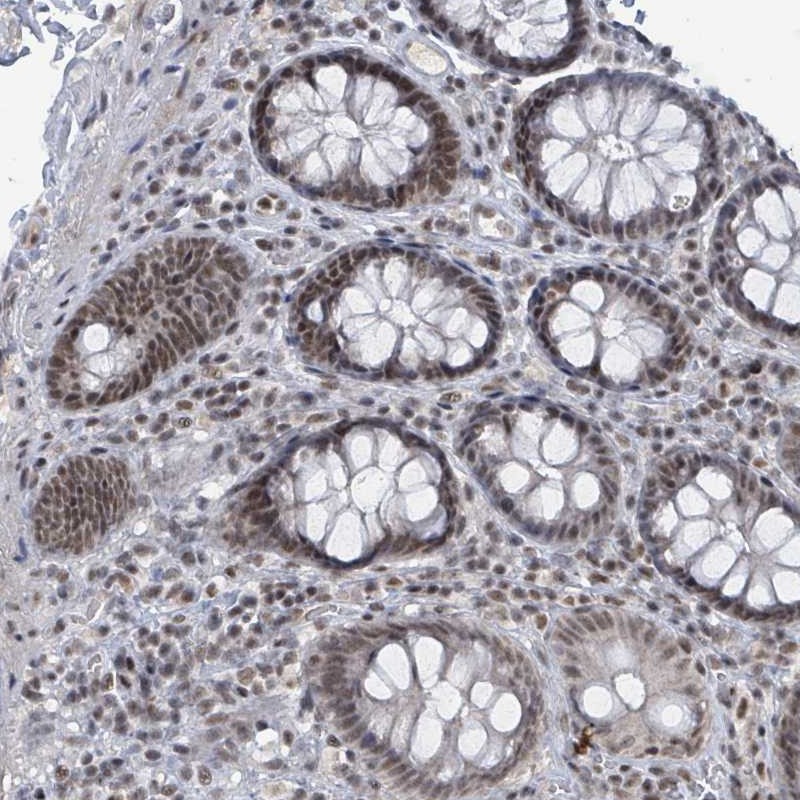

Immunohistochemical staining of human colon shows moderate nuclear positivity in glandular cells.